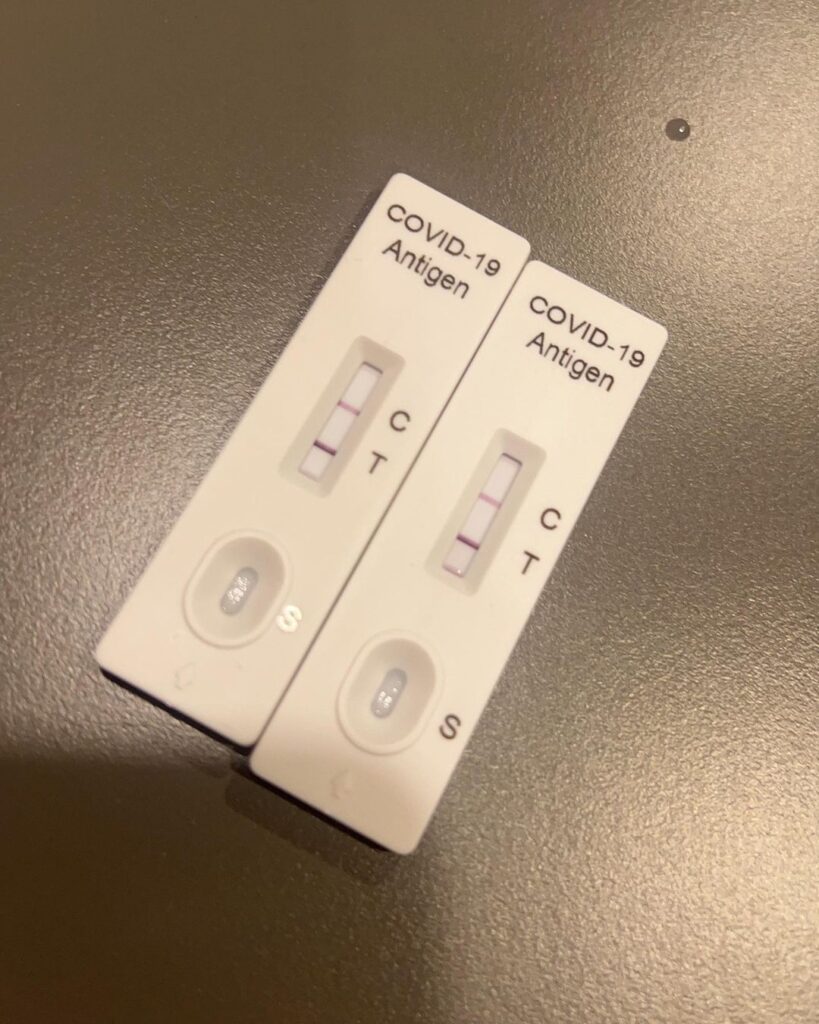

ต้องส่งกำลังใจให้รัวๆเลยทีเดียว เมื่อนักแสดงสาวว่าที่คุณแม่ป้ายแดงอย่าง “เกี่ยวก้อย-ขวัญกวินท์ เกิดลาภผล” กังวลอยู่ไม่น้อย เมื่อตนเองและสามี ผลตรวจยืนยันพบเชื้อโควิด-19 ขณะที่กำลังตั้งท้องได้ 4 เดือน

โดยเจ้าตัวได้โพสต์แจ้งข่าวผ่านอินสตาแกรมส่วนตัวพร้อมกับระบุว่า “สวัสดีโควิด🤢 ทำไมต้องมาเจอกันตอนท้อง 4 เดือนด้วยย!!! ระวังตัวมาตลอด สุดท้ายพลาดตอนทำงาน📹 ก่อนวันปิดตัว เศร้ามากกกก😭😭 ที่เศร้ากว่าคือแฟนติดด้วย และทำให้ครอบครัวแฟนกลายเป็นกลุ่มเสี่ยงไปด้วยเลย ขอโทษครอบครัวและผู้ใกล้ชิดนะคะ🙏🥹

ตอนแรกคิดว่าติดคนเดียว พอติดคู่เลยต้องมาแอดมิด 🙎♀️ อาการของก้อย (วัคซีน: Astra2 + Pfizer 1) คือ ไอหนักมาก 2 วันแรก เจ็บคอ แน่นจมูก มีไข้ ปวดหัว บอกเลยว่าเกือบตุยย😣 ยาต้านไวรัส ฟาวิพิราเวียร์แม่ท้องกินไม่ได้ ทุกอย่างเลยต้องรักษาตามอาการ

วันนี้วันที่ 4 แล้ว อาการค่อยๆดีขึ้นตามลำดับ ปอดยังปกติดี แม่ท้องท่านอื่นที่ติดโควิด แม้ไม่ได้รับยาต้าน แต่คุณหมอแจ้งว่าไม่ต้องกังวล อาการจะค่อยๆดีขึ้นเอง เอกซเรย์ปอดได้ถ้าจำเป็น แต่ต้องมีแผ่นตะกั่วปิดท้องให้น้องด้วยนะคะ